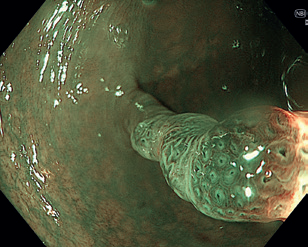

Obr. 10 Léze uchopená mukosektomickou kličkou.Endoskopická submukózní disekce (ESD) představuje další pokrok v resekcích neoplastických lézí s většími rozměry, které není možné odstranit endoskopickou slizniční resekcí en bloc. ESD, která byla vyvinuta v Japonsku pro léčbu časného karcinomu žaludku, umožňuje en bloc resekci i u větších lézí. Tato metoda spočívá v submukózní injekci následované cirkulární incizí sliznice okolo léze a postupnou disekcí v submukózní vrstvě pod lézí, což umožňuje získat en bloc vzorek bez omezení velikosti léze (obr. 12–14). Při výkonu se používá endoskop s nasazeným nástavcem („cap”) pro lepší přehled v terénu, samotná disekce se provádí pomocí různých typů specializovaných nožů, některé z nich mají i možnost přímé submukózní injekce během výkonu bez nutnosti měnit nástroj.